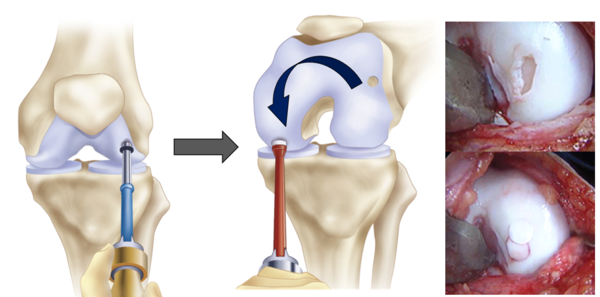

론조볼 또한 비교적 젊은 나이에 무릎연골관련 수술을 하고 난 후 결과가 좋지 않은 것 같습니다. 최근 2023년 3월 현지 기사에 의하면 2번의 수술로도 (아마 미세골절술) 결과가 좋지 못해 “연골 이식술 (Cartilage transplantation)”이라는 수술을 3번째 수술로 받았다고 보도되었습니다. 연골 이식술은 줄기세포 이식술과는 또 다릅니다. 손상부위의 연골과 뼈가 동시에 손상이 있어 재생능력이 없다고 판단될 때, 본인의 무릎 중에 사용을 하지 않는 연골과 뼈의 일부분을 동시에 떼어내 손상부위로 옮기는 수술입니다.